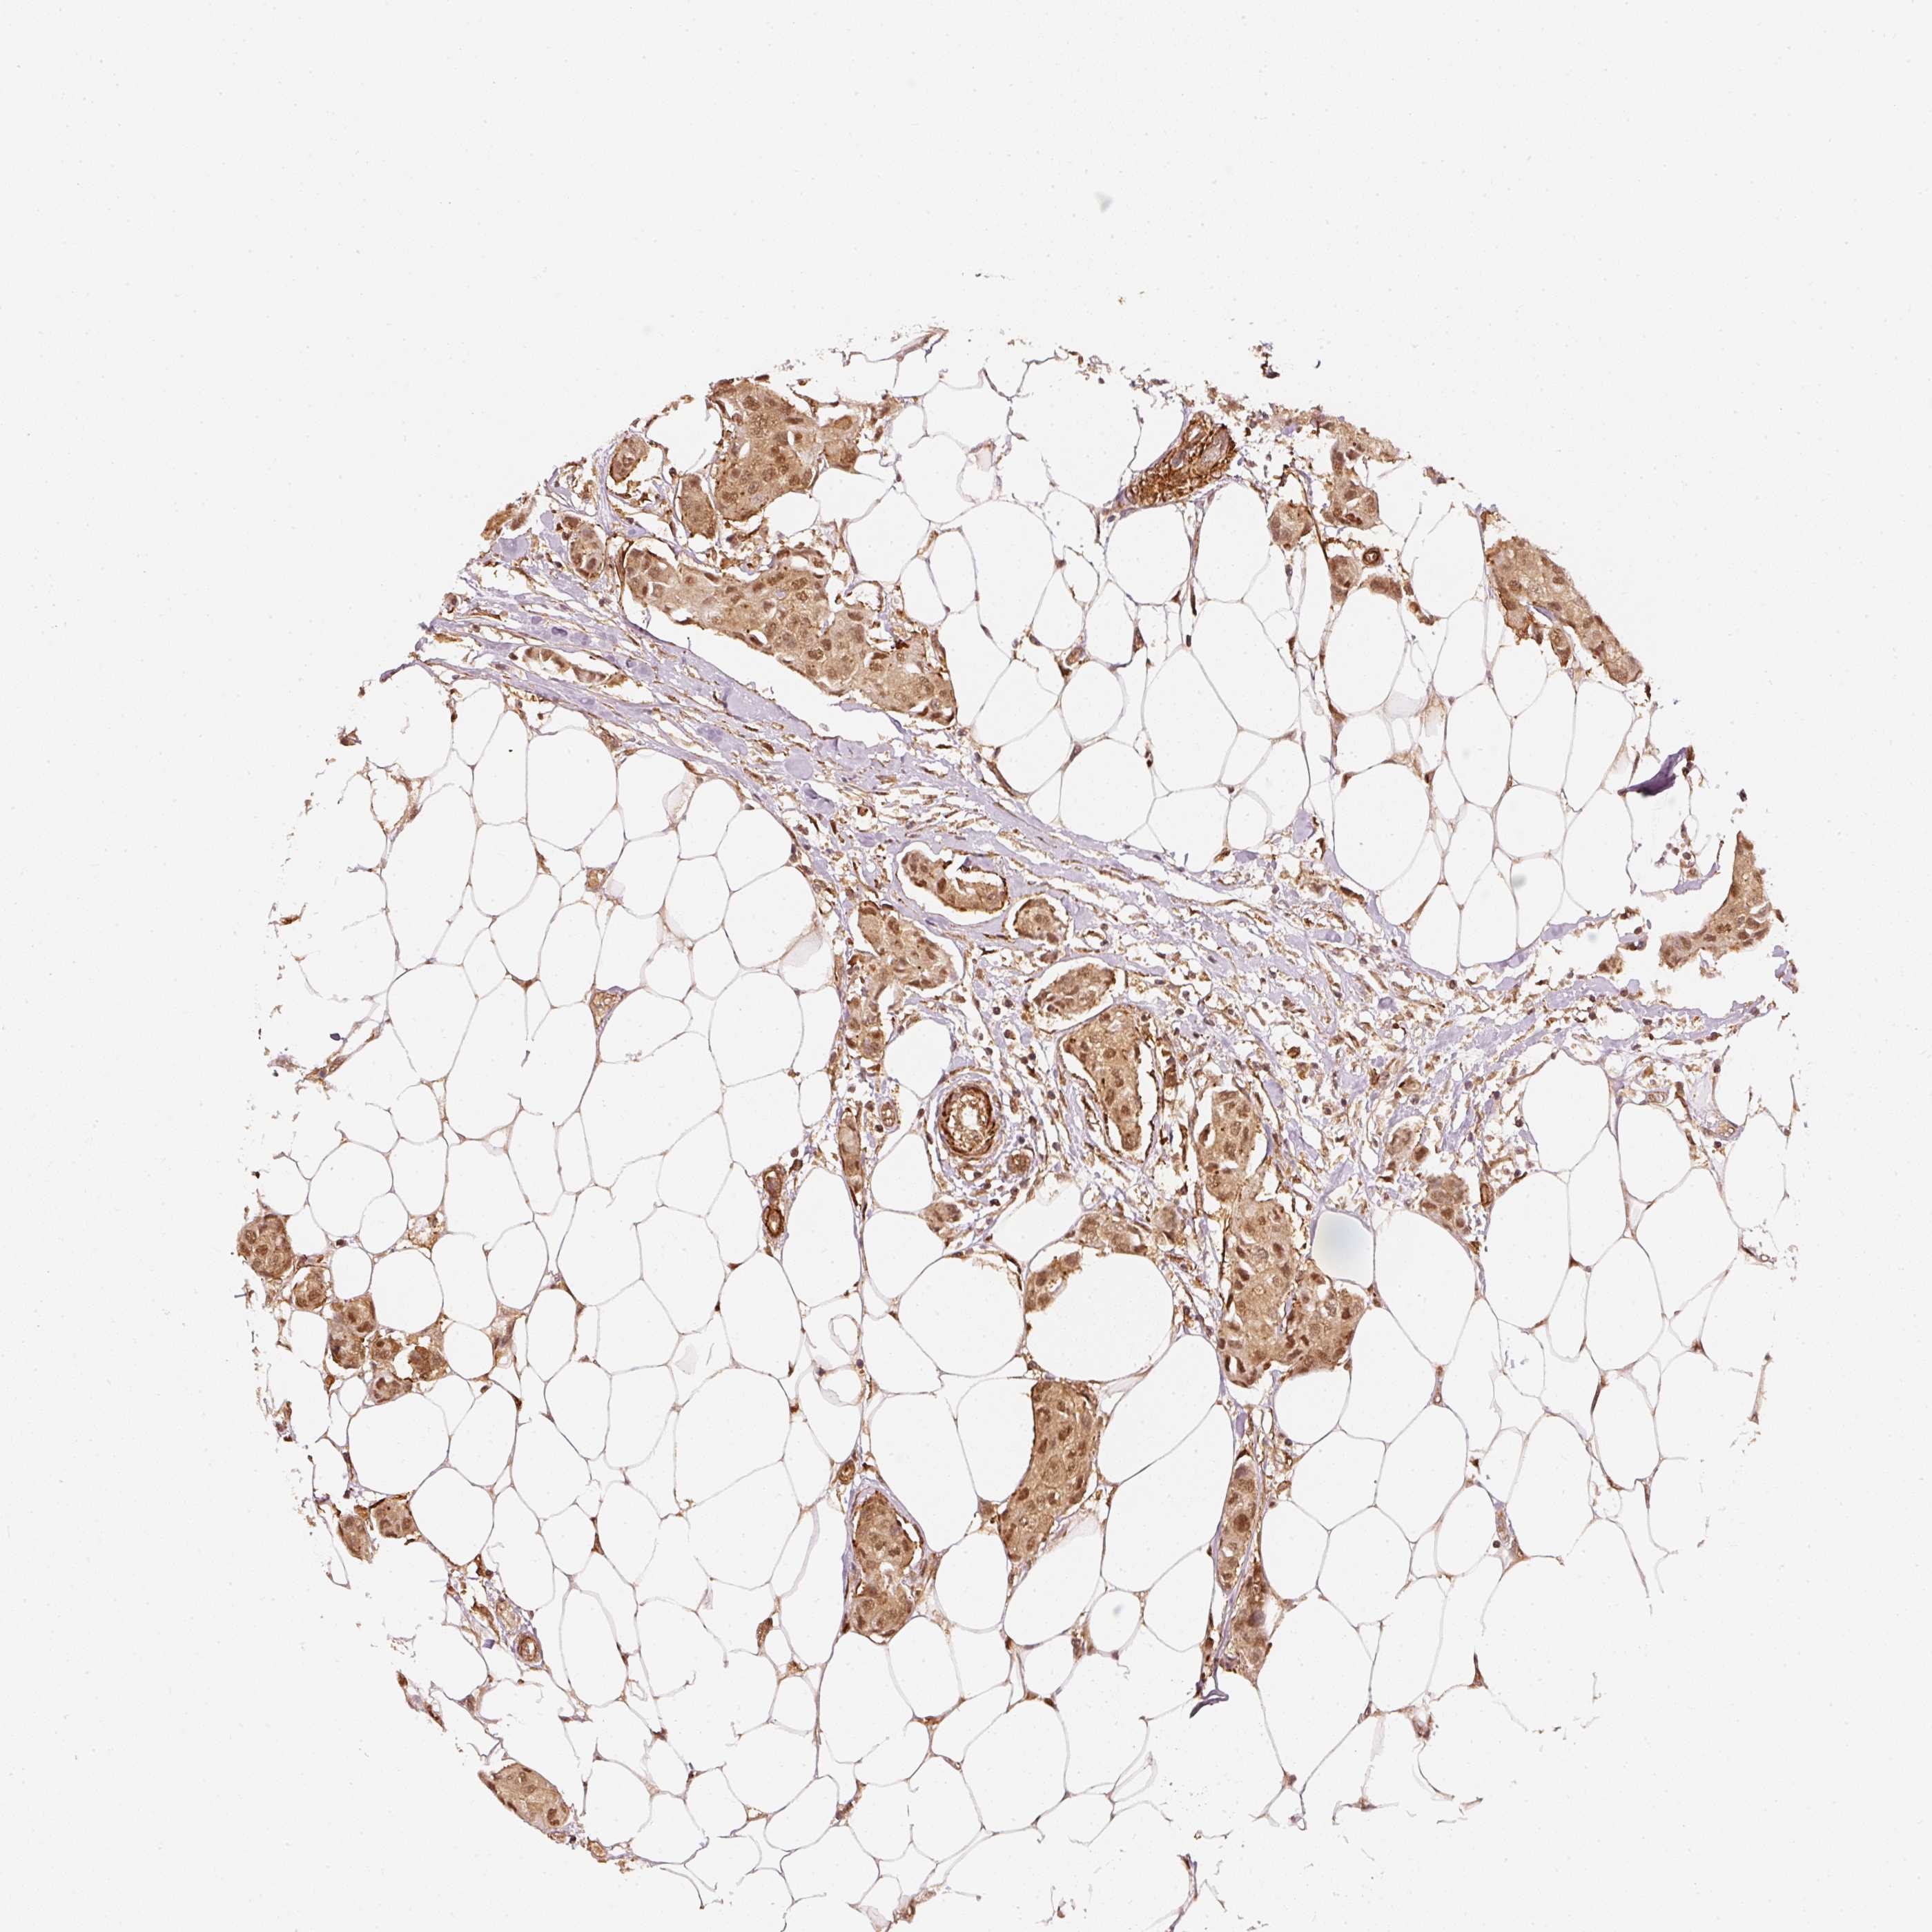

CANCER BREAST CANCER Show tissue menu

BRCA TCGA BRCA VALIDATION PROTEIN EXPRESSION